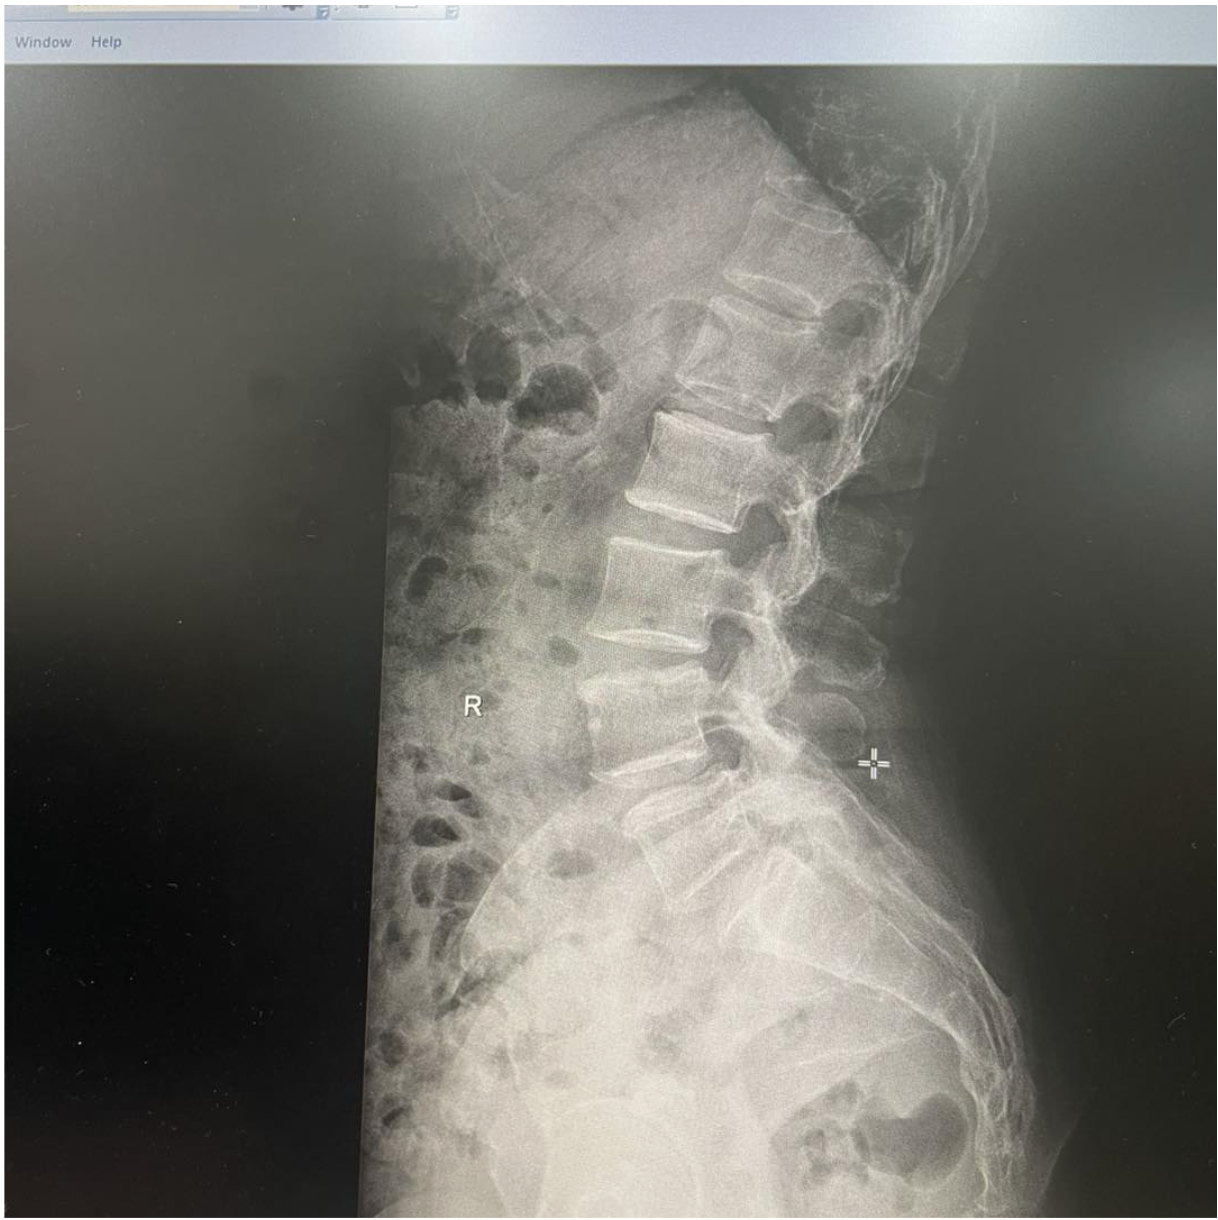

ส่งตรวจ X-ray บริเวณกระดูกสันหลังส่วนเอว (Lumbar spine) พบว่า: ช่องว่างระหว่างหมอนรองกระดูก L4–L5 และ L5–S1 แคบลง มีภาวะกระดูกเคลื่อน (spondylolisthesis) ของกระดูกสันหลังระดับ L5 เคลื่อนไปด้านหน้าในระดับ Grade 1

ซึ่งสอดคล้องกับอาการปวดร้าวจากหลังลงขาของผู้ป่วย จึงพิจารณาวินิจฉัยว่าเป็น หมอนรองกระดูกสันหลังกดทับเส้นประสาท (Lumbar disc herniation with nerve root compression)